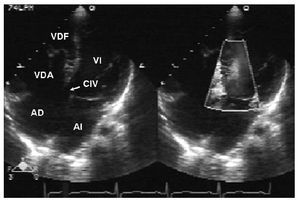

Figura 3 Ecocardiograma en vista apical de cuatro cámaras. Se observa un adosamiento de la valva septal de la tricúspide y comunicación interventricular; con el Doppler color se evidencia el paso de flujo a través de la comunicación interventricular. AD: aurícula derecha; AI: aurícula izquierda; CIV: comunicación interventricular; VI: ventrículo derecho.